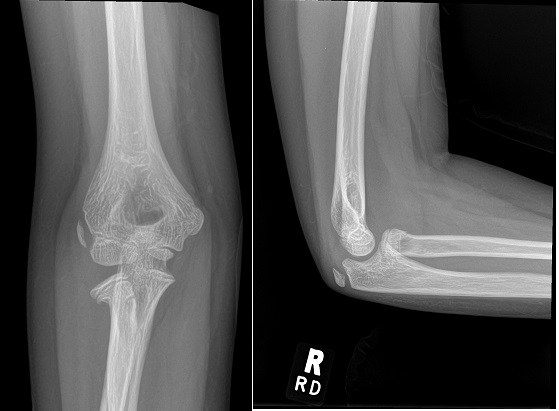

An 80 year old female presents to your office with a left ring finger deformity after a fall one week ago. She initially went to urgent care and xrays were unremarkable for a fracture (Figures 1 and 2). A photo of her left ring finger is shown in figure 3. On physical exam the left ring finger is in hyperextension at the PIP joint and flexion at the DIP joint. She able to flex her PIP joint with full motion. What is the best treatment option?